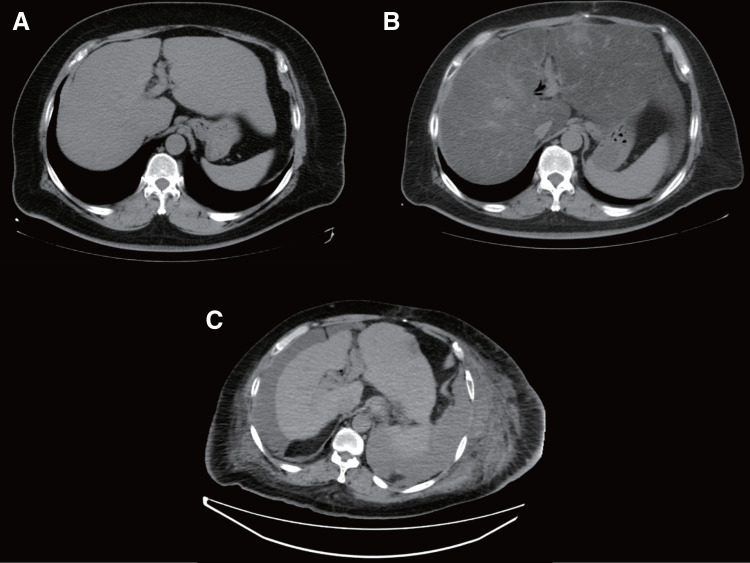

Case presentation: Case 1 was a 53-year-old man with obesity, metabolic-associated SLD (MASLD), and diabetes mellitus. The patient underwent PD for an intraductal papillary mucinous neoplasm. His liver function worsened and he developed decompensated LC 6 years later, eventually requiring LT. Due to poor mobility of the jejunal limb caused by severe adhesions and the presence of a pancreatojejunostomy, a choledochojejunostomy was performed at the more distal site of the common bile duct than usual. He developed hemobilia and biliary leakage but was discharged on POD 107. Liver function has been good for 2 years after LT without MASLD recurrence, although endoscopic treatment is periodically required for biliary stricture. Case 2 was a 46-year-old man with obesity, SLD, and a history of excessive alcohol consumption. The patient underwent PD for duodenal cancer. Five years later, he developed decompensated LC, which required living-donor LT. For biliary reconstruction, a new jejunal limb was created and elevated. He was discharged on POD 79. He has repeatedly developed cholangitis, but his liver function has been good for 6 years without SLD recurrence.